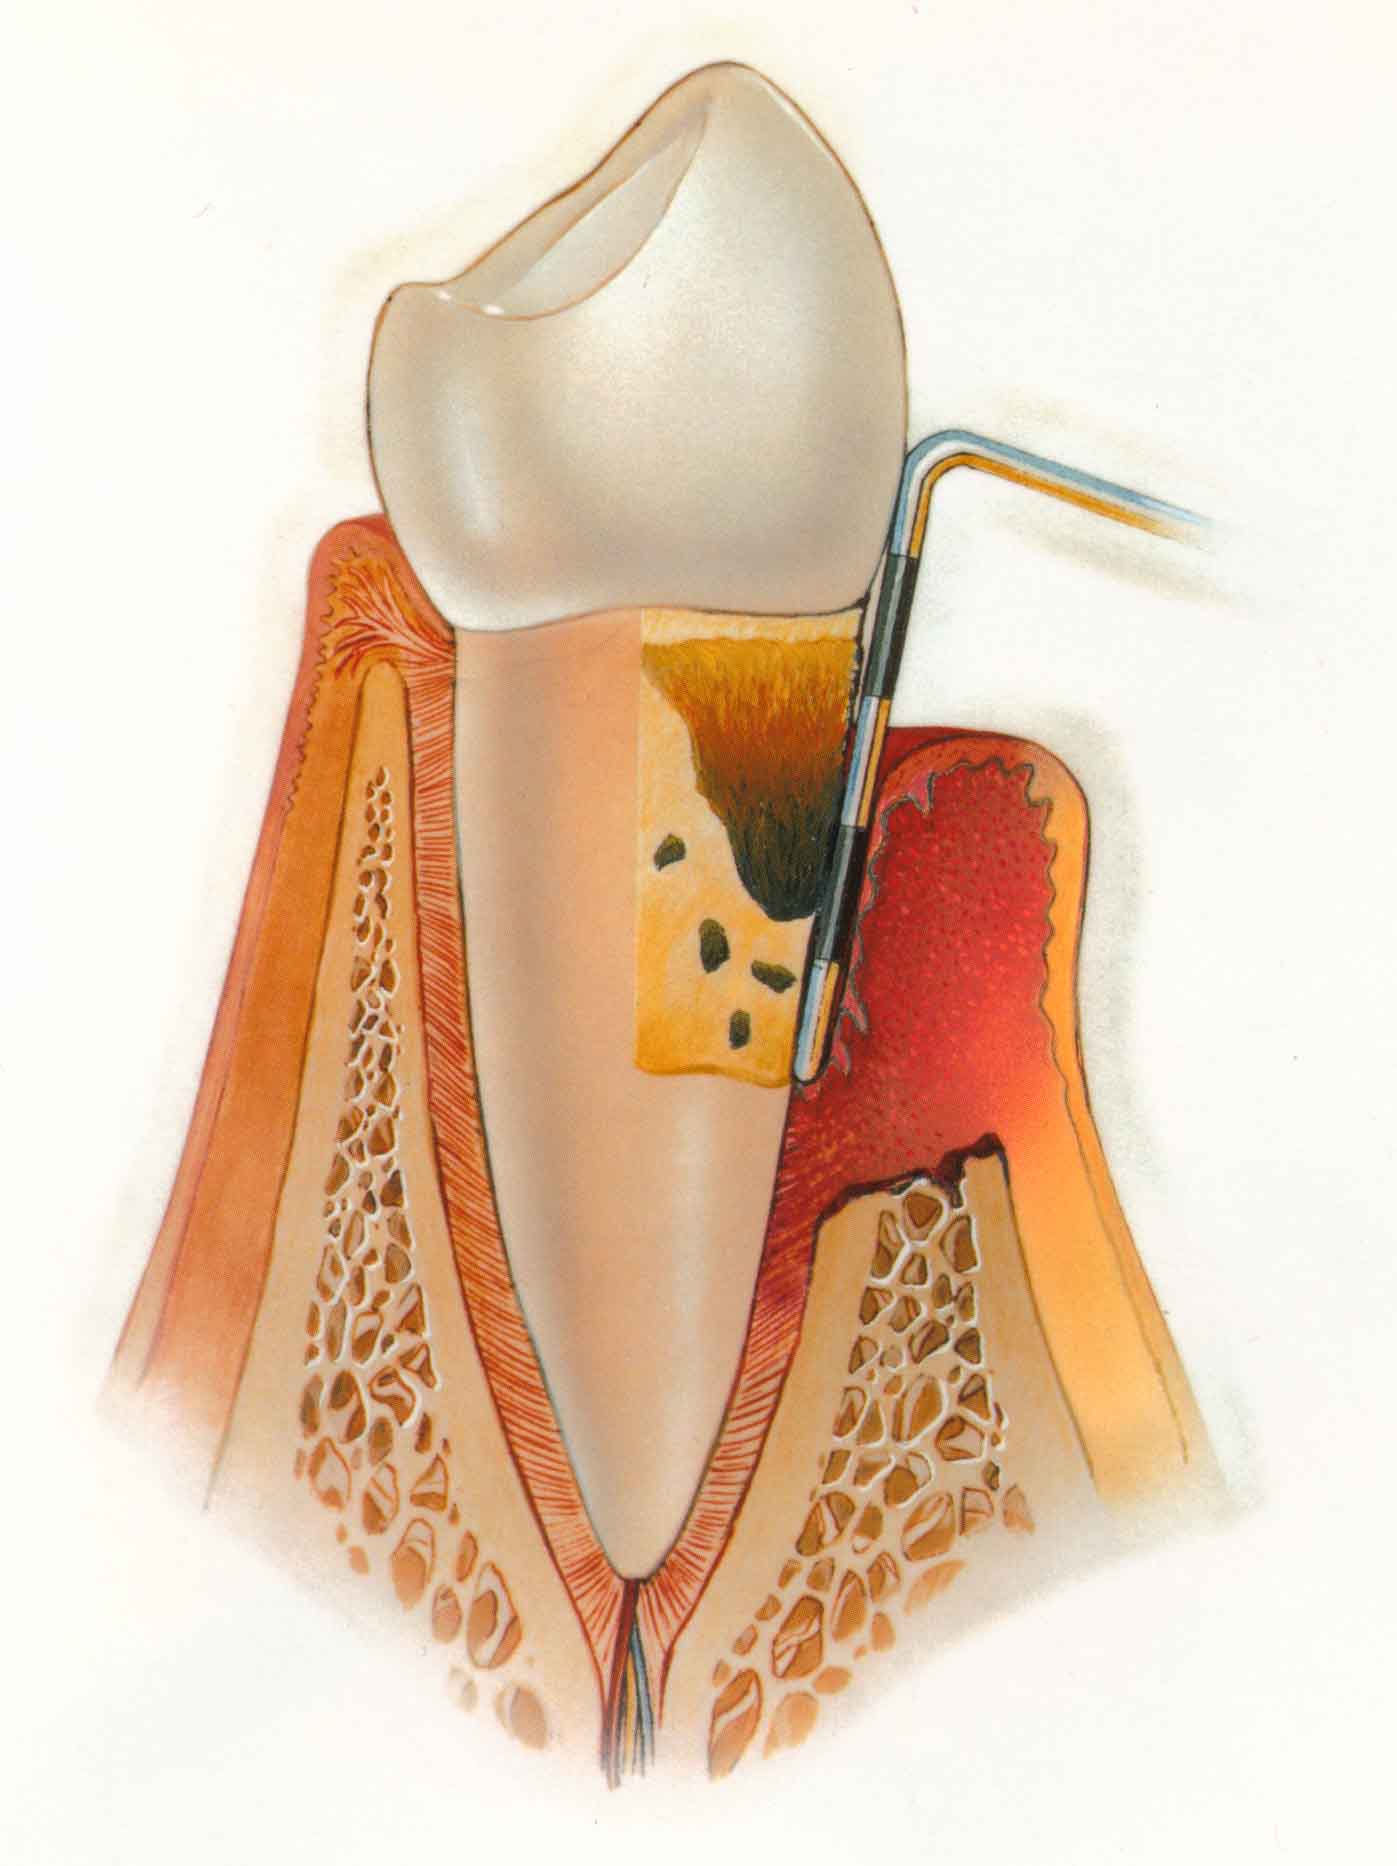

Periodoncia.

Tratamos las enfermedades de las encías como la gingivitis y la periodontitis con el objeto de eliminar la placa bacteriana y el sarro acumulado sobre y bajo las encías. Además cirugía periodontal para corregir recogimientos de encía, sacos periodontales profundos, compromisos de furcas, injertos de tejido conjuntivo y epitelial, etc.